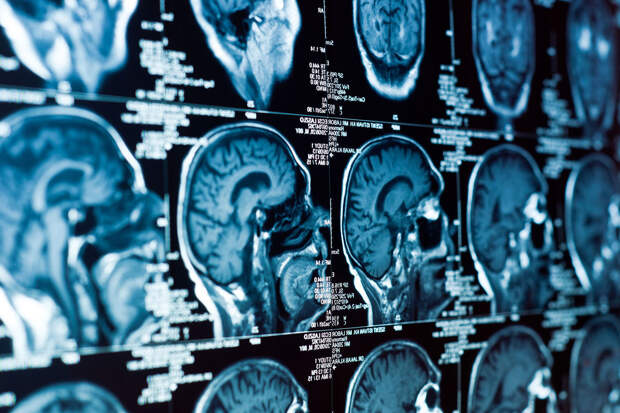

Длительное воздействие загрязненного воздуха может увеличивать риск развития доброкачественных опухолей головного мозга. К такому выводу пришли исследователи из Датского института рака в Копенгагене. Результаты работы опубликованы в Neurology Clinical Practice (NCP).

В исследовании участвовали почти 4 миллиона жителей Дании в среднем возрасте 35 лет. За 21 год наблюдений у 16 596 человек диагностировали опухоли центральной нервной системы, включая 4645 случаев менингиомы. Уровень воздействия загрязнителей оценивали с помощью адресных данных и компьютерного моделирования.

Менингиома — это опухоль, растущая из клеток паутинной мозговой оболочки. В большинстве случаев новообразование доброкачественное — оно не прорастает в окружающие ткани и не метастазирует.

После учета возраста, пола, образования и социально-экономического статуса оказалось, что риск менингиомы повышался на 10% при росте концентрации ультрадисперсных частиц на 5747 частиц в кубическом сантиметре.

Увеличение содержания мелкодисперсных частиц PM2,5 в воздухе на четыре микрограмма на кубический метр (мкг/м3) было связано с ростом риска на 21%. При воздействии диоксида азота (8,3 мкг/м3) вероятность развития менингиомы возрастала на 12%.

Связи с более агрессивными опухолями, такими как глиомы, обнаружено не было. Исследователи отмечают, что для подтверждения результатов нужны дополнительные работы. Однако, по словам ученых, улучшение качества воздуха может стать важным шагом в снижении риска опухолей мозга и укреплении здоровья населения.